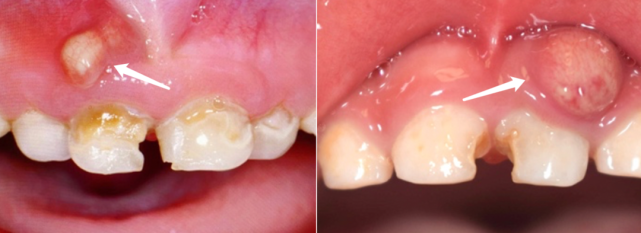

4岁的童童下牙龈长了一个包,家长看这个包和痘痘有几分相似,竟然上手给挤掉了!可没过几天,这个地方又鼓起了一个包,家长赶紧给童童吃消炎药。

然而,肿包却反反复复,到齿科一检查竟被告知:要做根管治疗。

龋齿导致的根尖周脓肿

看到这里,你是不是也很疑惑:牙龈长包干嘛要钻开牙齿做根管治疗?而且孩子才4岁,肯定害怕,不做行不行?

先看看下面这张图,是不是有点明白为啥要钻开牙齿做根管治疗了?

很多孩子牙髓感染,和“甜蜜的童年”有关。孩子上幼儿园后,各种零食、糖果打开了新世界的大门,也悄悄地满足了“小蛀虫”在牙齿上作祟的条件。

牙髓感染后,引起的炎症便能够一路蔓延,引起上图的恶果。

当然,除了蛀牙,磕伤牙齿也可能引起这样的脓包。这个年龄段的小朋友活泼好动,一不小心把门牙磕伤后,也容易造成牙根内部的牙髓坏死、发炎。

这种发炎引起的“脓包”,学名叫做根尖周脓肿。经过正规的根管治疗,它通常会很快消退(千万别上手挤!)。